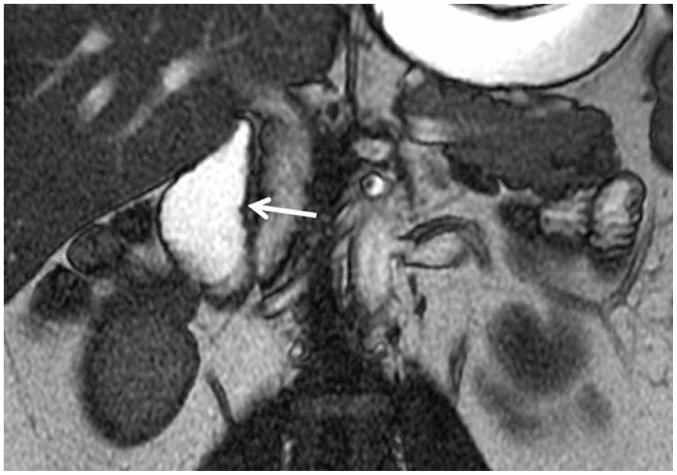

This pictorial review aims to illustrate the magnetic resonance imaging (MRI) findings and presentation patterns of anatomical variations and various benign and malignant pathologies of the duodenum, including sphincter contraction, major papilla variation, prominent papilla, diverticulum, annular pancreas, duplication cysts, choledochocele, duodenal wall thickening secondary to acute pancreatitis, postbulbar stenosis, celiac disease, fistula, choledochoduodenostomy, external compression, polyps, Peutz-Jeghers syndrome, ampullary carcinoma and adenocarcinoma. MRI is a useful imaging tool for demonstrating duodenal pathology and its anatomic relationships with adjacent organs, which is critical for establishing correct diagnosis and planning appropriate treatment, especially for surgery.